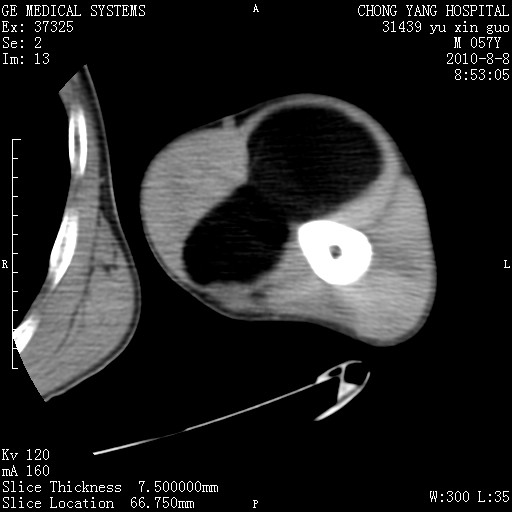

标题: CT28267:M57Y 上臂包块8年余。 [打印本页]

标题: CT28267:M57Y 上臂包块8年余。

上臂软组织内脂肪瘤。

包膜光滑、完整的脂肪密度肿块,支持脂肪瘤。